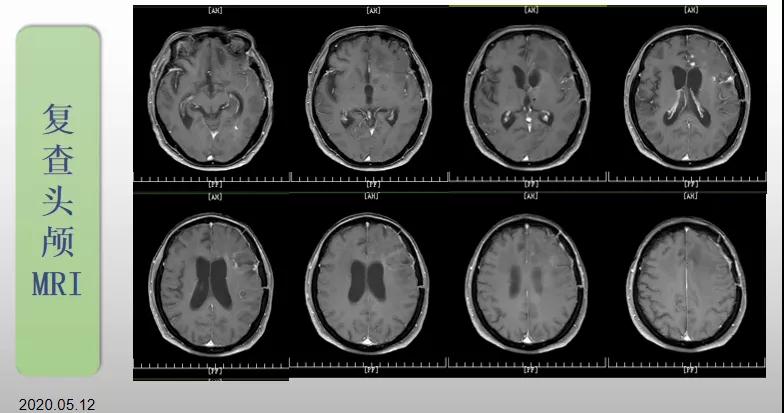

70歲的郝女士去年曾在外院查出“左額島葉”膠質(zhì)母細(xì)胞瘤(WHO Ⅳ級(jí)),并做了左側(cè)額島葉占位性病變切除術(shù)。術(shù)后進(jìn)行了同步放化療。由于治療條件有限,郝女士慕名來(lái)到我院就診。賀世明主任率領(lǐng)醫(yī)護(hù)團(tuán)隊(duì)立即為郝女士進(jìn)行了全面的檢查,決定為其進(jìn)行綜合治療 電場(chǎng)治療。經(jīng)過(guò)三個(gè)多月的綜合治療,患者復(fù)查頭顱MRI病變較前明顯縮小。出院時(shí),郝女士神志清醒,睡眠飲食正常,說(shuō)話很流利。“我是躺著進(jìn)來(lái)的,現(xiàn)在不用人攙扶,自己就可以走出病房了?!焙屡坷t(yī)護(hù)人員的手說(shuō)。